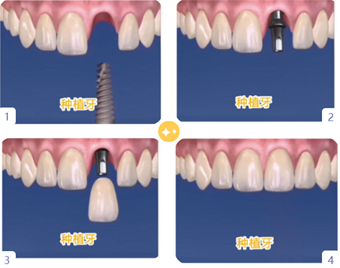

1.种植牙——“人类的第三副牙齿”

种植牙是让牙齿生根发芽吗?所谓“种植牙”,并不是一个生根发芽的过程,而是将种植体(人工牙根)通过手术植入缺牙区的牙槽骨内,一般经过3~6个月后,人工牙根与牙槽骨结合,连接基台戴上牙冠即可。而且种植牙无论从功能上,还是美观上,都非常接近人类的天然牙。

2.种植牙小演示